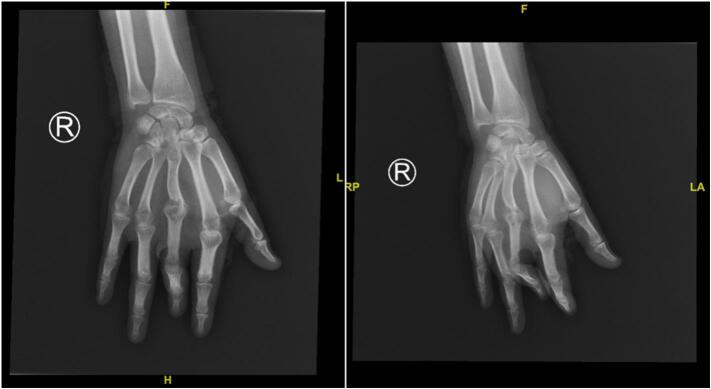

An 18-year-old patient presented with a painful, well-defined reddish plaque on the right palm, originating five years prior, accompanied by contractures of the middle finger. The tender lesion, characterized by an irregular surface, exhibited purulent discharge upon light touch through fissures along its periphery. Management involved necrotomy, debridement, and tissue biopsy for diagnostic and reconstructive purposes.

一名18岁患者右手掌出现一个疼痛、边界清晰的红色斑块,始于五年前,伴有中指挛缩。这个触痛的病变表面不规则,沿周边裂隙轻触时有脓性分泌物。治疗包括坏死组织切除、清创以及为诊断和重建目的进行的组织活检。